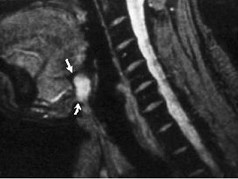

| 八岁患者,男性,因颈前正中包块6年入院,查体:颈前正中舌骨下方可触及一圆形包块,囊性,无压痛,随吞咽上下活动。 |

8.患者肿块图像及影像学检查结果见下图,本患者应考虑为 ( )![]() ![]() ![]() ![]() |

| 正确答案:8.A;9.A |